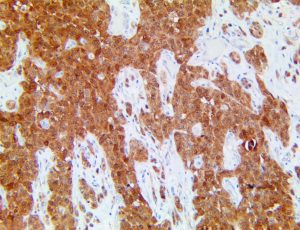

It is the ICU physician who is most likely to witness one of the deadliest manifestations of the abnormal immunological response, the cytokine storm syndrome (CSS). This response is also referred to by some as the cytokine release syndrome (CRS). CSS is characterized by continuous activation and expansion of macrophage and lymphocyte populations, which secrete large amounts of cytokines, causing the cytokine storm. This massive cytokine release is akin to hemophagocytic lymphohistiocytosis (HLH) disease, a syndrome characterized by initial unchecked and persistent activation of cytotoxic T lymphocytes and NK cells.

Clinical and laboratory manifestations of HLH include fever, enlarged liver and/or spleen, neurologic dysfunction, coagulopathy, liver dysfunction, cytopenias (i.e., low levels of erythrocytes, leukocytes, and/or platelets), hypertriglyceridemia, hyperferritinemia, hemophagocytosis, and eventually diminished NK cell activity as the immune system becomes progressively paralyzed. HLH can be familial (primary HLH) or secondary to another disease process (sHLH), such as rheumatic disease, in which it is referred to as macrophage activation syndrome (MAS, characterized by elevated ferritin).